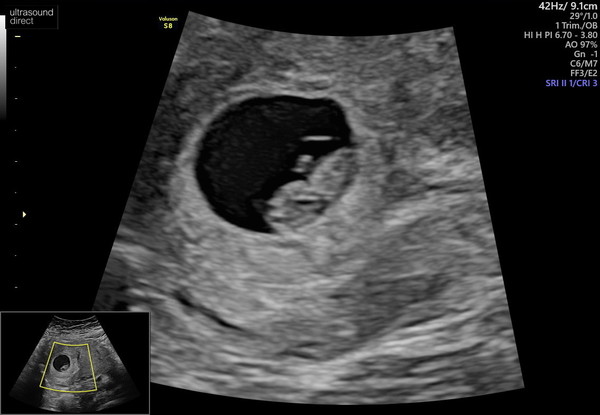

Also been for a scan today everyone 8+3 they dated me but I’m still going off my own date. 8 weeks today

@Londonaries according to my LMP im measuring same as you but I went in for a early scan yday as im so impatient all they seen was a sack at this point and told me to re book (it was a private scan).. jus want to know when did you conceive..